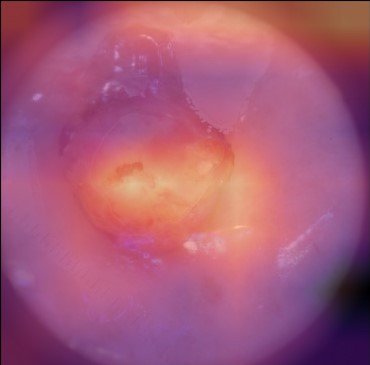

State-of-the-art deep learning approaches for skin lesion recognition often require pretraining on larger and more varied datasets, to overcome the generalization limitations derived from the reduced size of the skin lesion imaging datasets. ImageNet is often used as the pretraining dataset, but its transferring potential is hindered by the domain gap between the source dataset and the target dermatoscopic scenario. In this work, we introduce a novel pretraining approach that sequentially trains a series of Self-Supervised Learning pretext tasks and only requires the unlabeled skin lesion imaging data. We present a simple methodology to establish an ordering that defines a pretext task curriculum. For the multi-class skin lesion classification problem, and ISIC-2019 dataset, we provide experimental evidence showing that: i) a model pretrained by a curriculum of pretext tasks outperforms models pretrained by individual pretext tasks, and ii) a model pretrained by the optimal pretext task curriculum outperforms a model pretrained on ImageNet. We demonstrate that this performance gain is related to the fact that the curriculum of pretext tasks better focuses the attention of the final model on the skin lesion. Beyond performance improvement, this strategy allows for a large reduction in the training time with respect to ImageNet pretraining, which is especially advantageous for network architectures tailored for a specific problem.

翻译:在皮肤损伤识别方面,最先进的深层学习方法往往要求就更大规模、更多样化的数据集进行预先培训,以克服因皮肤损伤成像数据集规模缩小而产生的一般限制。图像网通常用作预培训数据集,但其转移潜力受到源数据集和目标皮肤科情景之间领域差距的阻碍。在这项工作中,我们采用新的预培训方法,按顺序培训一系列自我监视学习的借口任务,只要求不贴标签的皮肤损伤成像数据。我们提出了一个简单的方法,以建立一个命令来界定一个托辞任务课程。对于多级皮肤损伤分类问题和ISIC-2019数据集,我们提供了实验性证据,表明:一) 由一个托辞任务课程比个人托辞任务预先训练的模式更优于模型,这在图像网上培训模型比模型先培训更优于模型。我们证明,这一业绩收益与以下事实有关:一个更突出托辞任务的重点,即界定一个托辞任务课程,确定一个托辞任务大纲。对于多级皮肤损伤分类问题,以及ISIC-2019数据集,我们提供了实验性地证明:一模型预设的模型的模型预设型模型预训练模型,使得最终的升级模型能够改进。